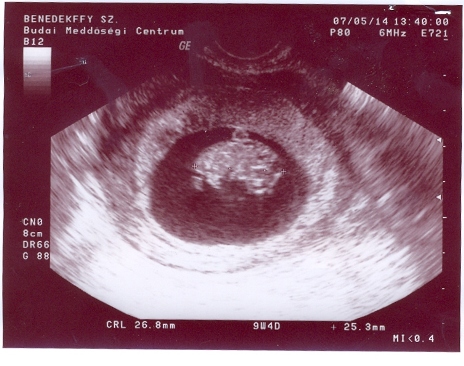

Csajok!

Itt vannak és az enyémek!!!!!!

26,8mm-es az egyik a másik 25,3mm-es.Méhszáj zárt,koruknak megfelelőek és már most hyperaktívak voltak,annyit mozogtak!